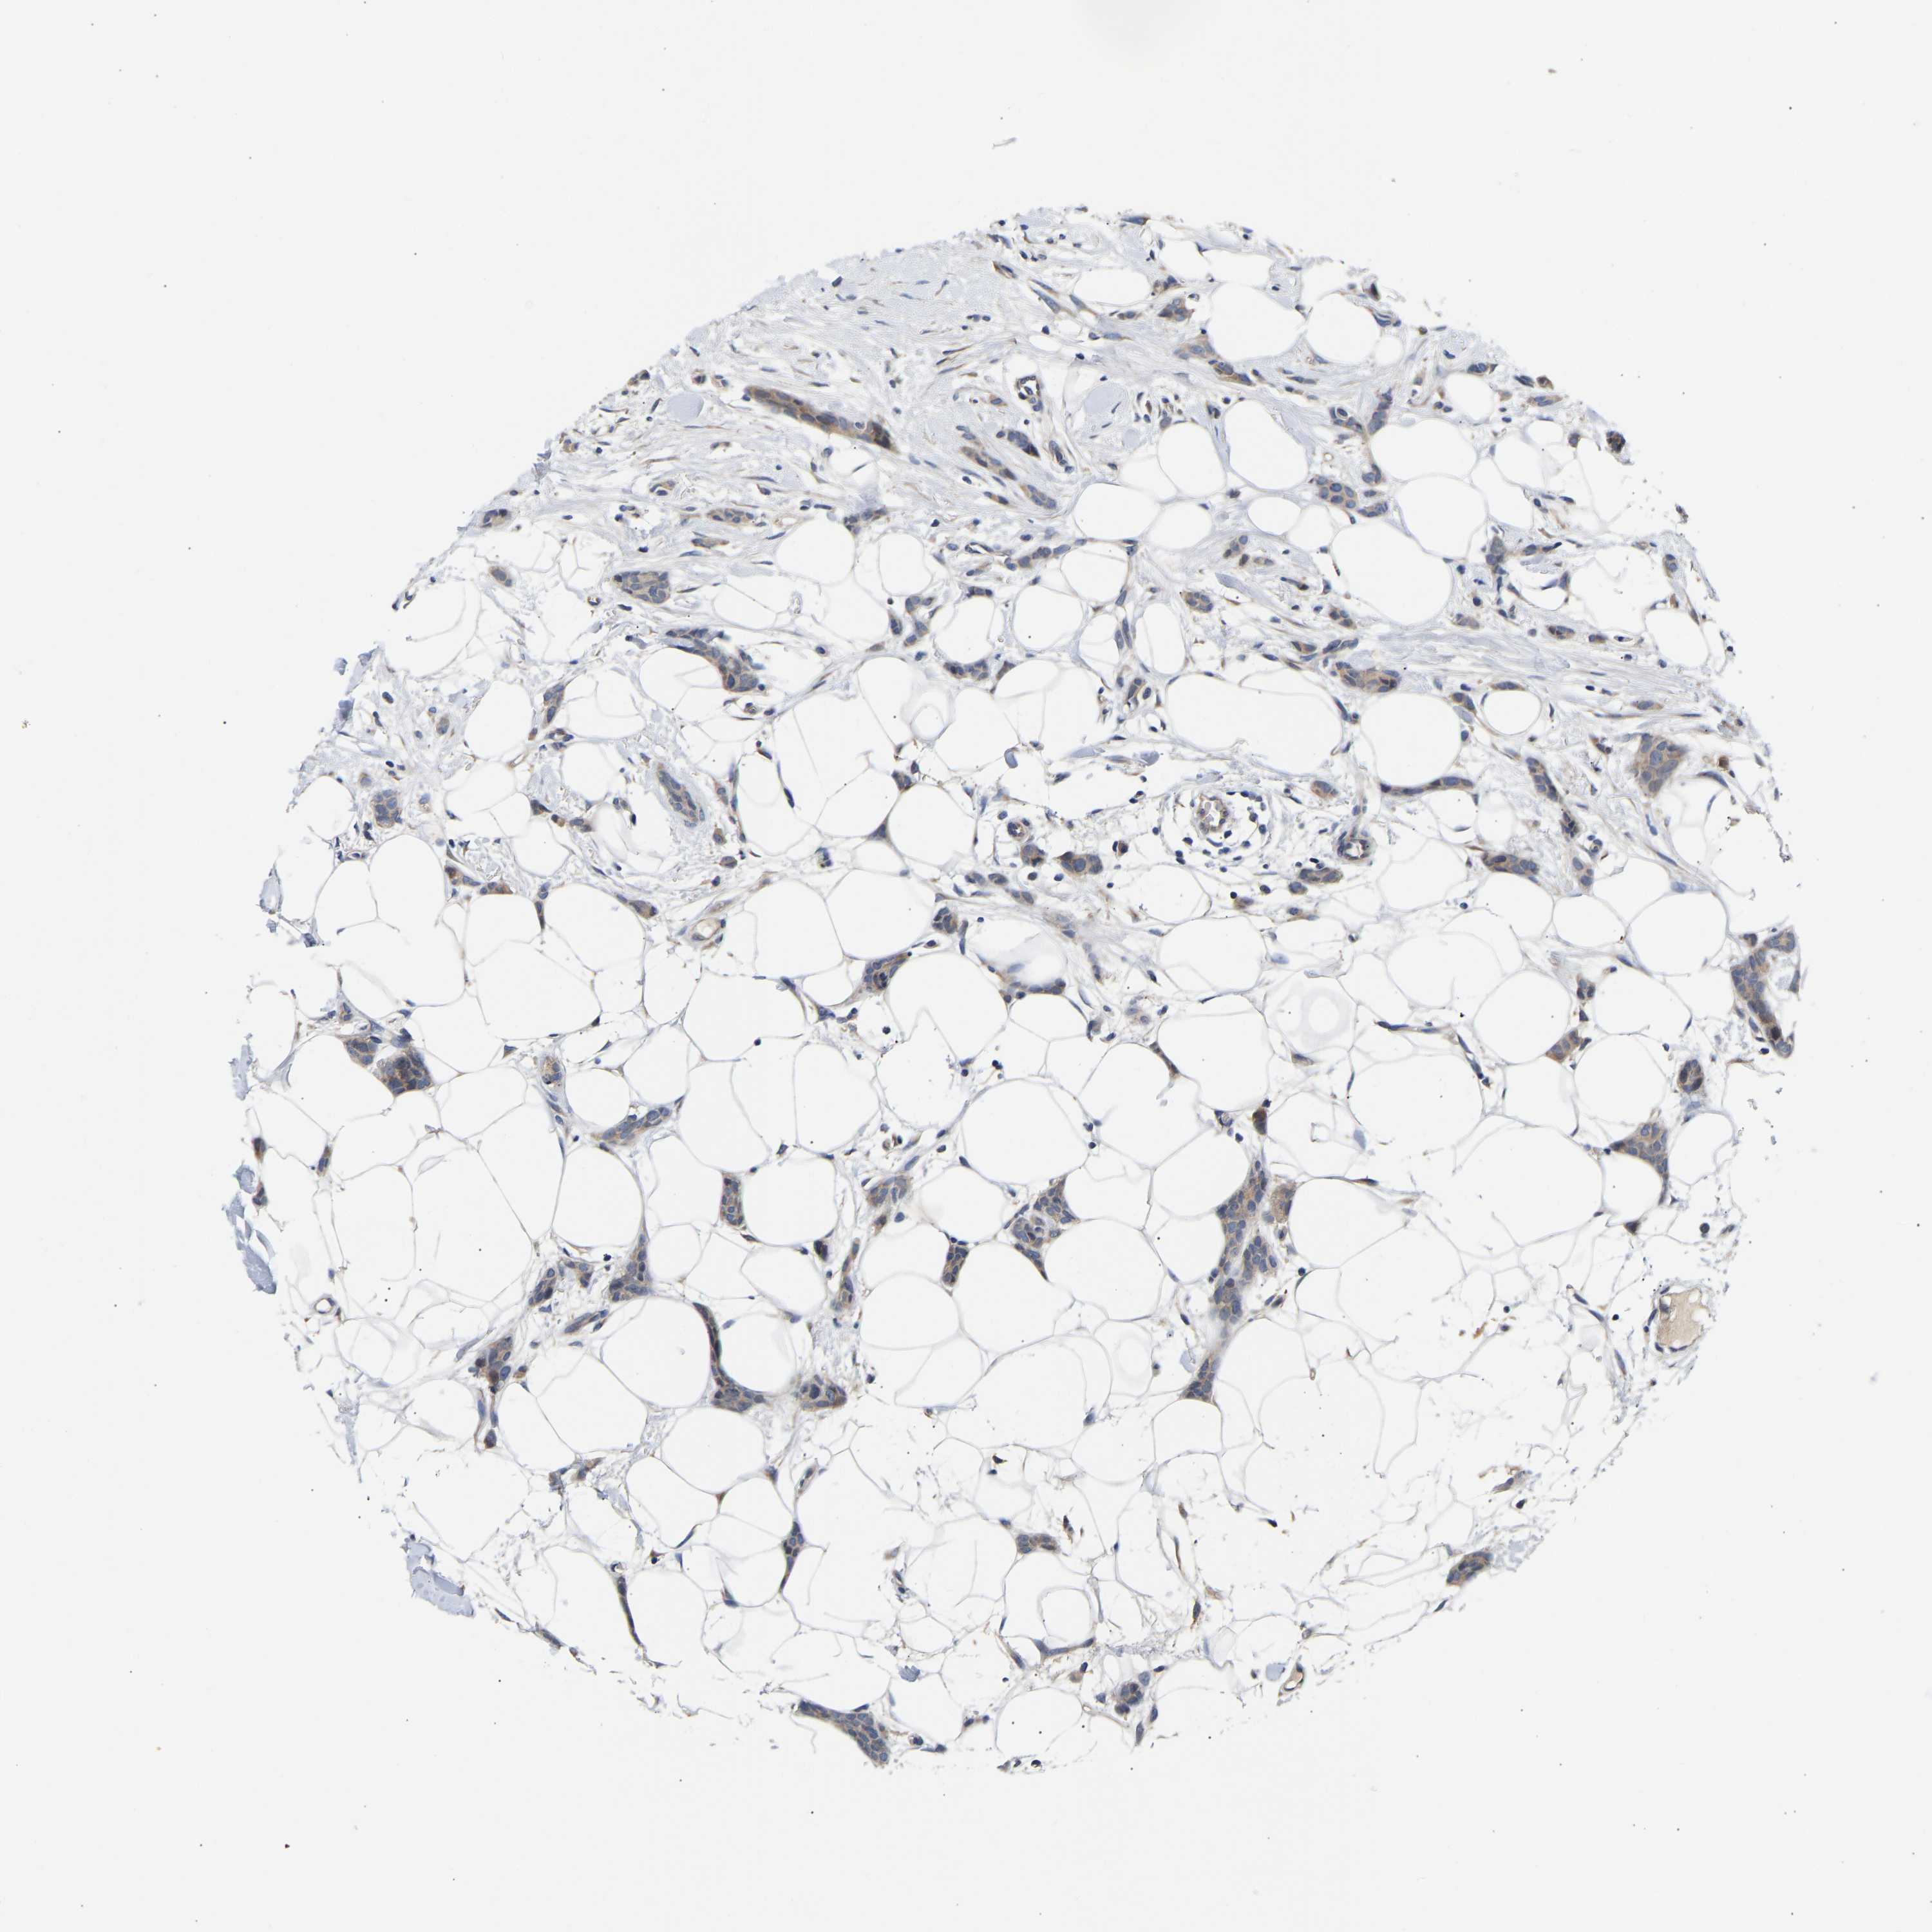

CANCER BREAST CANCER Show tissue menu

BRCA TCGA BRCA VALIDATION PROTEIN EXPRESSION